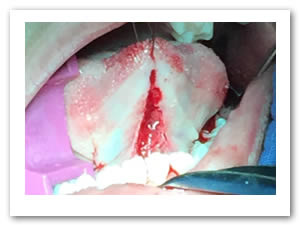

• Se realizó una incisión horizontal en la parte media del frenillo con hoja de bisturí No. 15 y mango No. 3, posteriormente se comenzó a cortar el frenillo de arriba abajo cuidando la anatomía de la región y la zona de las carúnculas sublinguales de los conductos de Wharton y Rivini. (Figuras 5 y 6).

Figuras 5 y 6. Incisión y corte del frenillo.